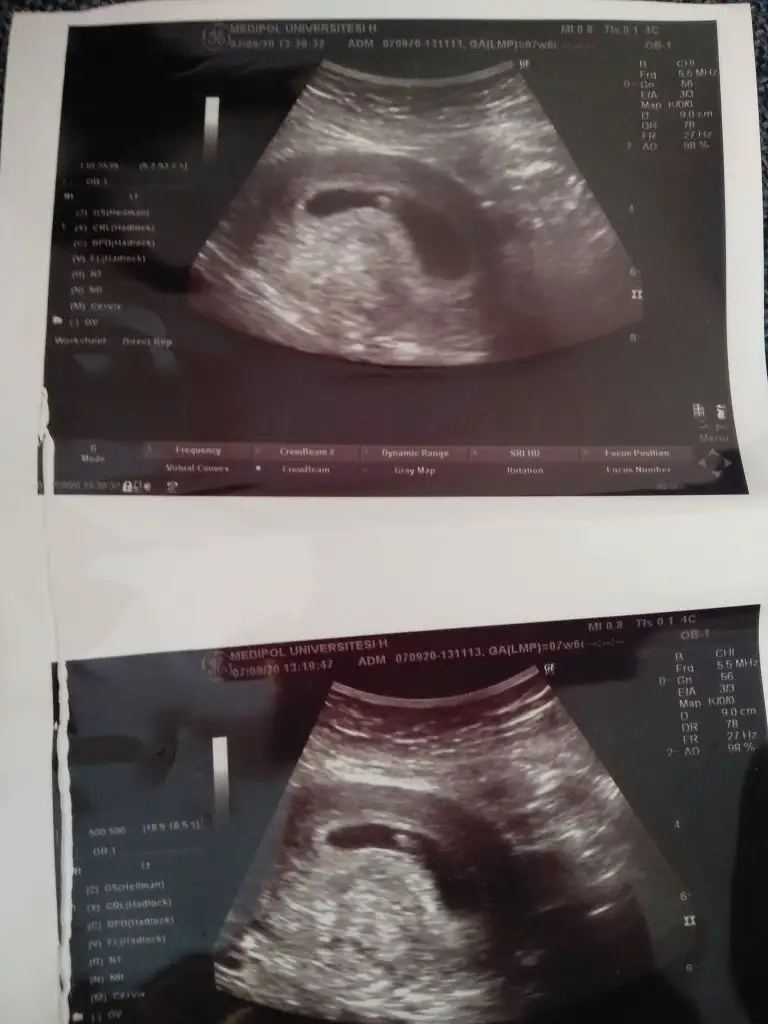

Bebek sol da değil mi canım.Hani kiz sağda erkek solda yazıyor ilk sayfada.Kız buna göre tabiki en iyi 11 12 13 haftalar olmalı

Yolk saç neredeyseBebek sol da değil mi canım.Hani kiz sağda erkek solda yazıyor ilk sayfada.

Birde vajinal USGBebek sol da değil mi canım.Hani kiz sağda erkek solda yazıyor ilk sayfada.

Anladım vajinal olduğunu görmedim çok pardon.Bu yolk sac olayı falan beni aşar.Birde vajinal USG

Kız gibi buna göreÇok teşekkür ederim. Aynı gün çekilmiş bir usg daha var. Orda da sağa yakın görünüyor.